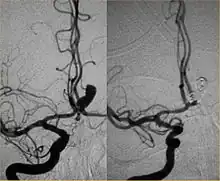

Parallel to the development of catheters, in the radiology and neuroradiology units, image technology dramatically improved: Charles Mistretta in 1979 invented digital subtraction angiography (DSA), the technique currently in use. It consists of performing skull radiography under basic conditions which are then "subtracted" to the image after contrast media injection, to provide an image where only brain vessels are displayed, with great improvement in the diagnostic potential.

Between the end of the 1980s and the beginning of the '90s, INR was suddenly revolutionized after the work of two Italian physicians: Cesare Gianturco and Guido Guglielmi. The first combined a deep knowledge of diagnostic radiology with a great ability to solve technical and manual problems. He invented Gianturco's coils, which he used to make the first attempts to embolize arteries and aneurysms.[8] Gianturco also patented the first endovascular stent approved by the American FDA;[8] a device with a great legacy. In the second half of the 1980s, Sadek Hilal was the first in Columbia University to use coils to treat brain aneurysms; but this technique was inaccurate and dangerous because the coils were released with little control with great risk of occluding the vessel from which the aneurysm originated (parent vessel).[9] The coil embolization was revolutionized by the work of Guido Guglielmi in UCLA, who realized that electricity could function as a controlled release mechanism for coils; in 1991 he published two works dealing with the embolization of brain aneurysms by means of detachable platinum coils[10] (Guglielmi's coils). The treatment of aneurysms was thus made more accessible and safe.

New techniques: Sole stenting and flow diversion stents

From the early 2000s, intracranial stents were used to prevent the coils inside the aneurysmal sac from protruding into the parent artery.[11][12] Flow diversion devices were later developed, with the function of reconstructing the vessel's normal anatomy without directly closing the aneurysm neck and therefore preserving side branches and preventing ischemia.[13] The sole stenting[14] procedure involves the insertion of a stent only (without any coils) into the vessel that has an aneurysm.[15]